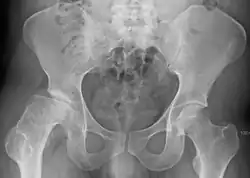

| Radiograph of a person with Legg–Calvé–Perthes disease | |